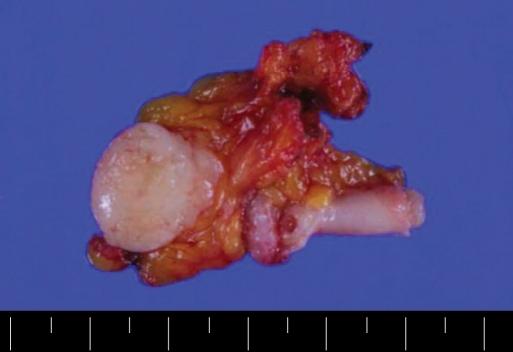

腹腔镜手术治疗阑尾神经鞘瘤1例

Laparoscopic approach to a case of appendicular schwannoma.

Appendicular schwannoma is a rare tumor originating from Schwann's cells in the Auerbach plexus. The preoperative diagnosis is difficult because the clinical features are nonspecific, and it is mostly found accidentally via a radiologic image as a tumor, mimicking malignancy. We report a case of an appendicular schwannoma coexisting with an adenocarcinoma in the lung. A laparoscopic appendectomy was done with a clear resection margin, and the immunohistochemical staining showed positive S-100 protein, which confirmed the schwannoma. The patient also underwent a left upper lobectomy of the lung. The patient has been free of recurrence for the 6 months since the operation. The laparoscopic approach could be available for treatment of an appendicular schwannoma, thus avoiding an unnecessary laparotomy.

摘要

阑尾神经鞘瘤是一种罕见的肿瘤,起源于奥尔巴赫神经丛的施万细胞。术前诊断困难,因为其临床特征不具有特异性,大多是在影像学检查时偶然发现为肿瘤,类似恶性肿瘤。我们报告一例阑尾神经鞘瘤与肺腺癌并存的病例。行腹腔镜阑尾切除术,切缘清晰,免疫组化染色显示S-100蛋白阳性,确诊为神经鞘瘤。患者还接受了左肺上叶切除术。术后6个月患者无复发。腹腔镜手术可用于治疗阑尾神经鞘瘤,从而避免不必要的开腹手术。